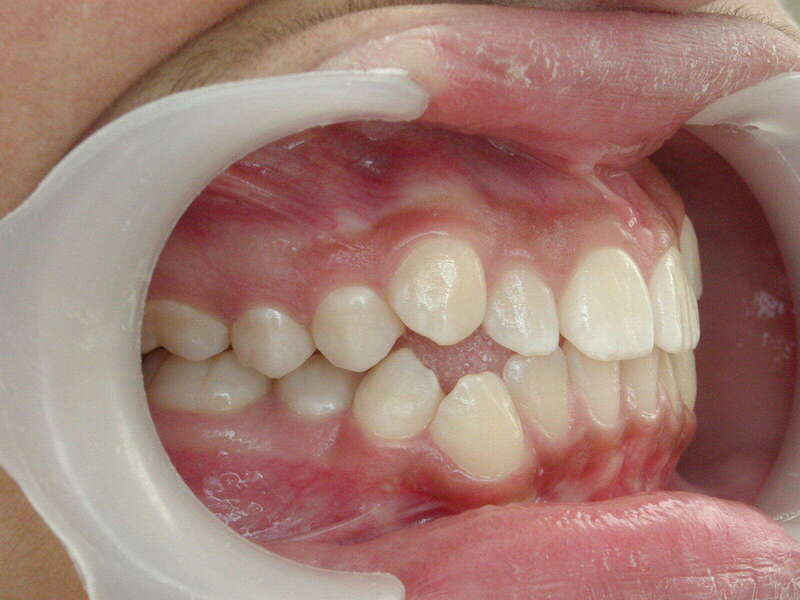

Cas n°2 traité par disjoncteur - enfant

Ce cas d’orthopédie précoce chez un enfant de 8 ans illustre l'efficacité du protocole Disjoncteur + Masque de Delaire. Le patient présentait une inversion d'articulé avec un proglissement mandibulaire, une situation pathologique risquant d'aboutir à un excès de croissance irrémédiable de la mâchoire inférieure.

Le traitement a permis une expansion et une protraction du maxillaire supérieur. En replaçant le maxillaire en avant de la mandibule, l'orthodontiste a levé le verrouillage mécanique et "remis la croissance sur les rails".